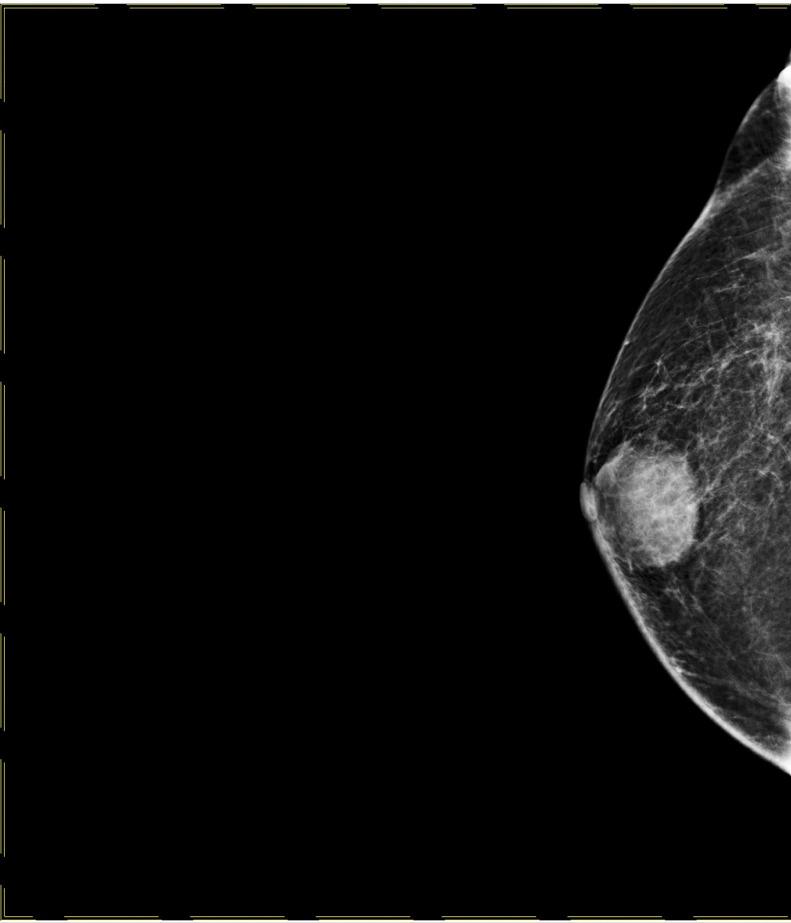

Breast abscess in males is a rare condition, which accounts for 1%-3% of all documented breast diseases. Males with certain risk factors may develop a breast abscess. The ultrasonographic, mammographic, and pathological characteristics of this case will be highlighted in the report. A 51-year-old morbidly obese Saudi male who is a 160-pack-years smoker presented to our surgical clinic complaining of a right breast mass that presented a long time ago and was changing in size. The mass was painless until 5 days prior to presentation. On physical examination, a firm nonmobile 3 × 4 cm mass was felt at 10-12-o'clock, 1 cm away from the nipple. A bilateral X-ray mammogram and ultrasound were performed with fine needle aspiration and culture. The mammogram of the right breast showed a well-circumscribed subareolar mass with equal density, and it was also associated with overlying skin thickening and relative breast parenchymal edema. The fine needle aspiration grossly showed yellowish-green turbid content followed by turbid blood. The anaerobic culture results showed the gram-positive cocci, Finegoldia Magna. The patient was then instructed to take an antibiotic accordingly and return after 1 week. Fine needle aspiration and culture were performed again after antibiotics and grossly showed 2-3 cc of pus without any growth in culture. Male breast disorders are typically benign, with gynecomastia being the most prevalent, and malignancy being the most serious despite its rarity. Breast abscesses are a challenging clinical condition, and radiologists have a pivotal role in evaluation and follow-up of these lesions.

男性乳腺脓肿是一种罕见疾病,占所有已记录乳腺疾病的1% - 3%。具有某些危险因素的男性可能会发生乳腺脓肿。本病例的超声、乳腺X线摄影及病理特征将在报告中重点阐述。一名51岁的沙特男性,病态肥胖,有160包年的吸烟史,因右乳肿块前来我们的外科门诊就诊,该肿块出现已久且大小有变化。在就诊前5天肿块一直无痛。体格检查时,在距乳头1厘米处的10 - 12点位置可触及一个3×4厘米、质地坚硬、固定不动的肿块。进行了双侧乳腺X线摄影、超声检查以及细针穿刺抽吸和培养。右乳的乳腺X线摄影显示乳晕下有一个边界清晰、密度均匀的肿块,同时伴有皮肤增厚和乳腺实质相对水肿。细针穿刺抽吸物肉眼可见黄绿色浑浊内容物,随后为浑浊血液。厌氧菌培养结果显示为革兰氏阳性球菌,大芬戈尔德菌。随后指示患者相应地服用抗生素,并在1周后复诊。使用抗生素后再次进行细针穿刺抽吸和培养,肉眼可见2 - 3毫升脓液,培养无生长。男性乳腺疾病通常为良性,男性乳房发育症最为常见,尽管恶性肿瘤罕见,但却是最严重的。乳腺脓肿是一种具有挑战性的临床病症,放射科医生在这些病变的评估和随访中起着关键作用。